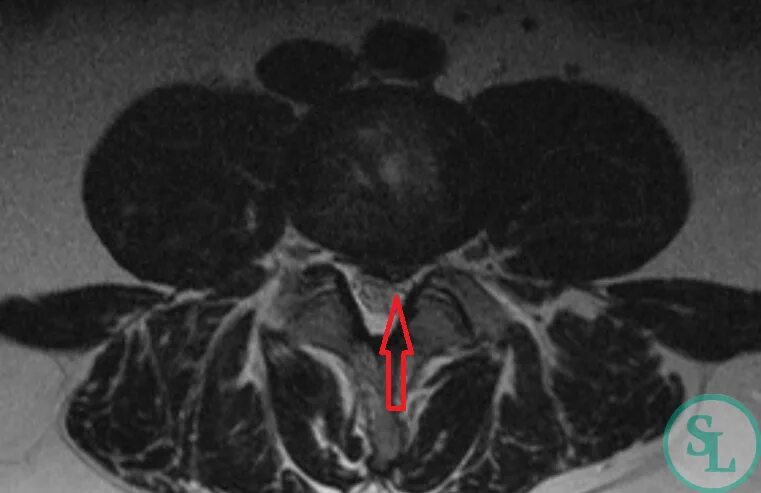

Узлы шморля в грудном отделе что это